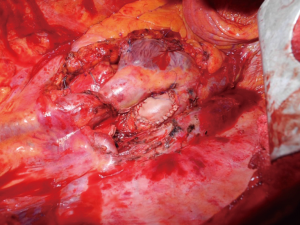

尽管肺癌伴心脏转移往往被视为无法手术治疗,但在完全切除似乎可行且没有远处转移的情况下也偶尔行手术治疗。鉴于非常少量的文献病例报道,手术的适应证仍有争议 [6,7,19-25]。大多数现有的病例关注了左心房切除。解剖学上,因为右肺静脉更短,右侧肿瘤侵犯左心房比左侧肿瘤快。此外,左侧肿瘤快速多器官浸润(左心房、主动脉、食道等)更常见,因此排除了采取手术的选择。心脏停搏液或细波室颤与体外循环联合使用使得可以安全打开心腔,辅助肿瘤的完全切除。一些作者[19,24,25]描述了使用 Sondergaard 技术解剖房间沟,可以延长左心房袖带,然后安全地夹住,从而无需使用体外循环即可进行左心房切除术;然后可以直接缝合心房缺损或插入心包补片以重建心房壁(图2)。